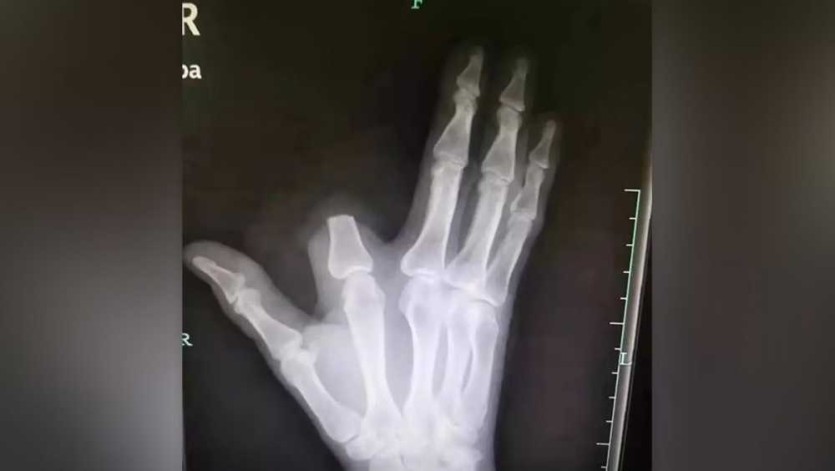

중국 저장성에 거주하는 60세 농부 장씨는 산에서 작업을 하던 중 독사에게 손가락을 물렸습니다.

그는 이 뱀이 물리면 다섯 걸음 안에 죽는다는 전설의 '오보사'라고 판단하고, 독이 퍼지는 것을 막기 위해 자신의 검지 손가락을 즉시 절단했습니다.

이후 그는 절단된 부위를 천으로 감싸고 80km 떨어진 항저우 시내 병원을 찾아갔습니다.

병원에 도착한 장 씨를 진찰한 의사들은 "손가락을 자를 필요가 전혀 없었다"고 말했습니다.

장 씨는 급하게 병원을 오느라 잘라낸 손가락을 산에 그대로 두고 왔습니다.

이 때문에 의료진은 그의 손가락을 다시 붙여줄 수 없었습니다.